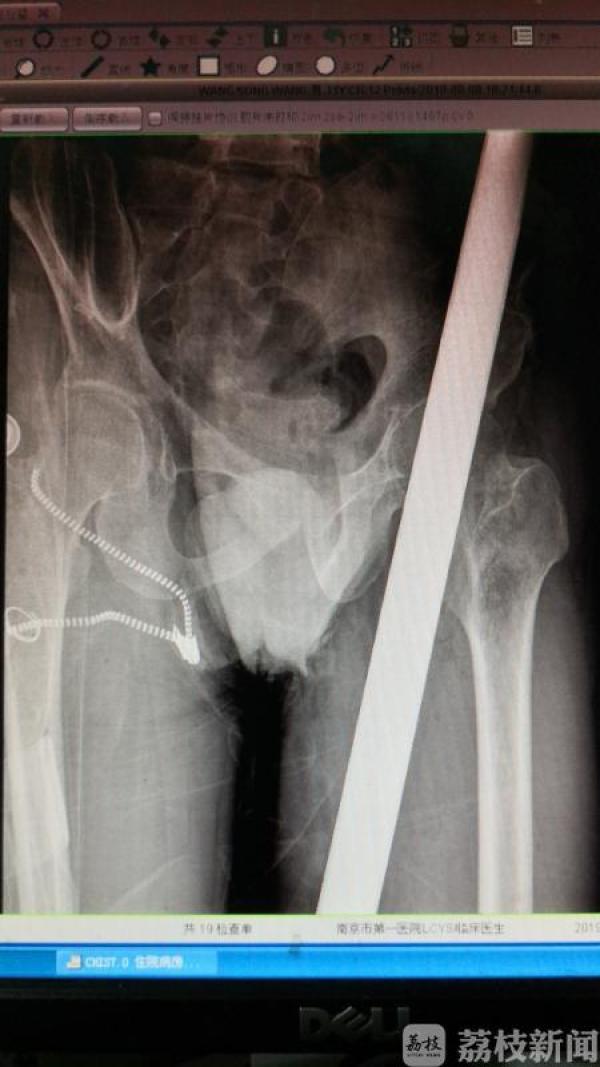

41岁的李先生(化名)是一名建筑工人,9月8日下午5点半,他在工地从8米高处坠落,一根直径10厘米,长一米多的钢管贯穿其左腿和臀部。幸运的是,钢管与坐骨神经和盆腔“擦肩而过”,经南京市第一医院骨科、麻醉科、重症医学科等多科医生奋力抢救,李先生在这罕见的人体贯穿伤里侥幸生还,手术10天后可以下地站立。目前李先生已经康复出院。

接诊的南京市第一医院骨科副主任医师杨蓊勃介绍:“当时遇到了一个非常棘手的问题,钢管露在上面是1/3,中间身体里是1/3,从臀部出来又是1/3,不管从哪一头拔都不好。钢管外面还套了塑料套,两头都很大,直接拔是没有办法拔出的。”

手术医生杨蓊勃决定,在保护重要脏器的情况下,用手从里往外推出钢管。这个动作必须要快,而且保持平稳,避免造成二次伤害。骨科副主任医师吴晓曙正好前一台手术刚结束,主动留下来参与手术。两位专家通过手工切开钢管侧面的肌肉,把肌肉拉开以后,把钢管用无菌敷料包好推出体外,整个过程不到半个小时。

杨蓊勃说,幸运的是,钢管基本没有伤及到重要器官,离坐骨神经就差一公分,只要再偏一点就能把盆腔击穿,坐骨神经如果打断,左腿也就面临截肢的危险。

钢管取出以后,专家立刻为其准备手术。取管后,被钢管压迫的血管得到释放,这让手术台上的医生捏了一把汗,为避免血管出血,医生快速将出血血管缝合。整个手术仅用了一个小时。